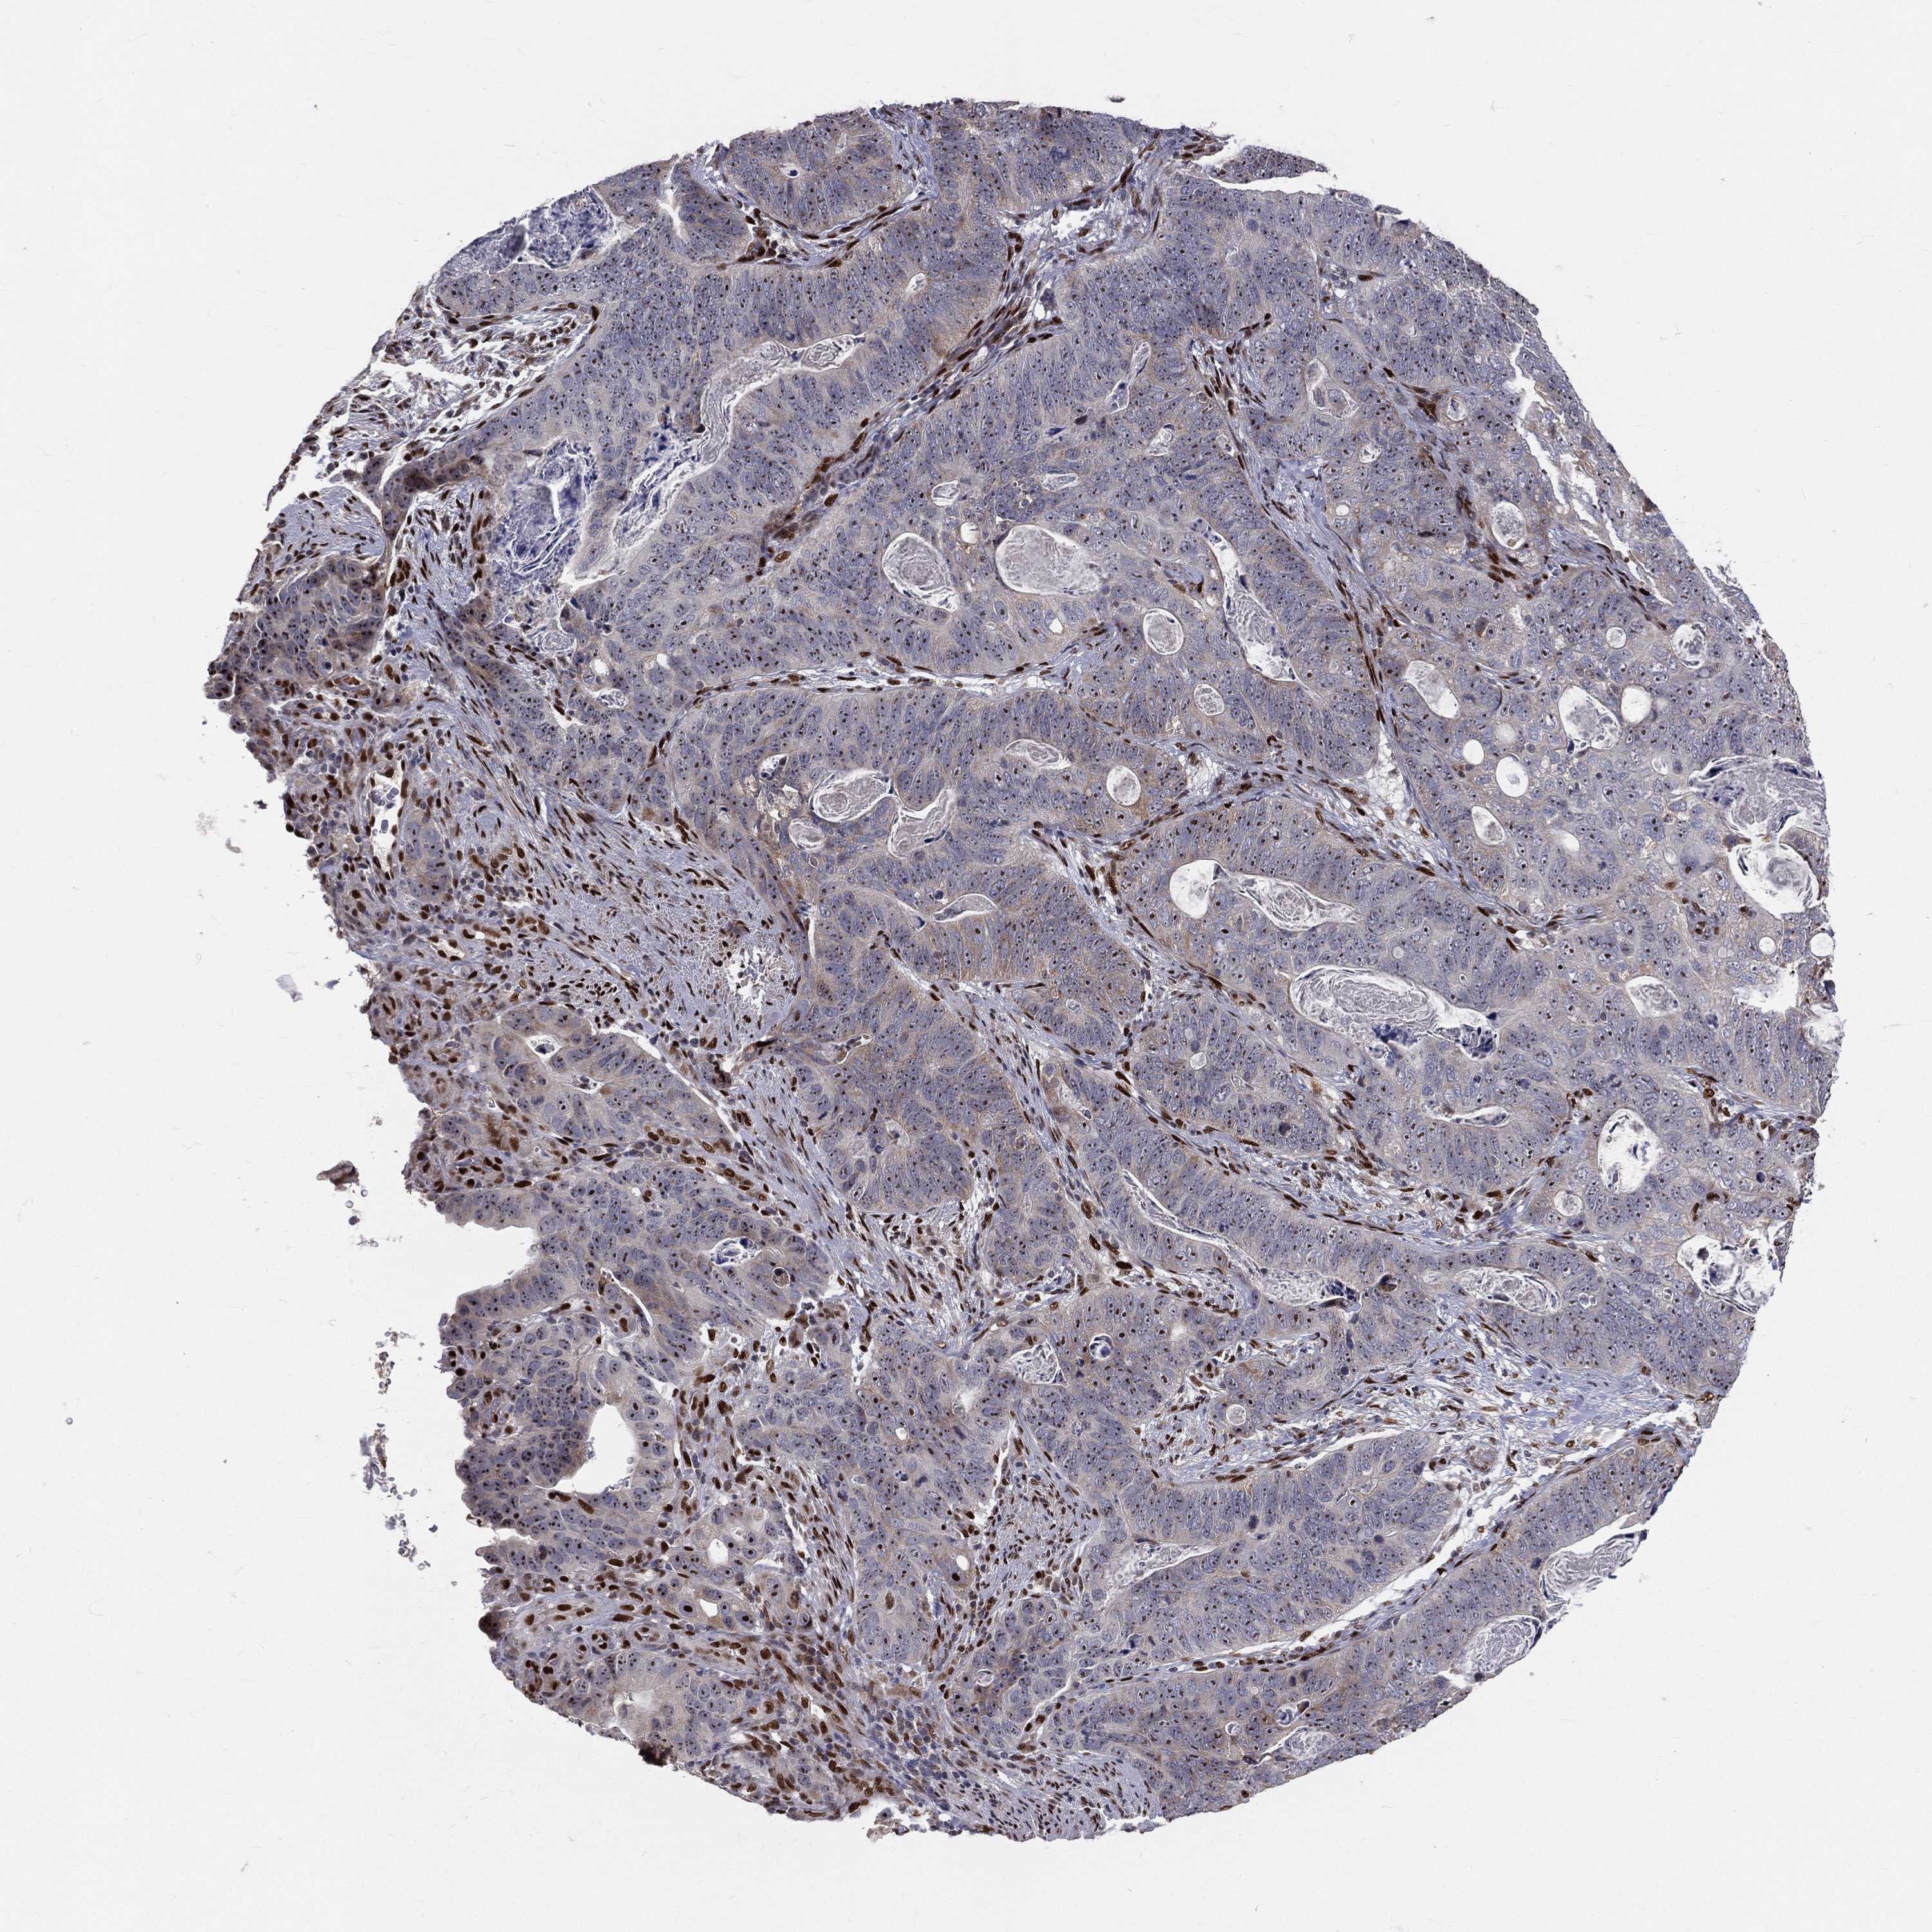

STOMACH CANCER - Protein expressioni

A mouse-over function shows sample information and annotation data. Click on an image to view it in a full screen mode. Samples can be filtered based on level of antibody staining by selecting one or several of the following categories: high, medium, low and not detected. The assay and annotation is described here.

Antibody stainingi

Antibody staining in the annotated cell types in the current human tissue is reported as not detected, low, medium, or high, based on conventional immunohistochemistry profiling in selected tissues. This score is based on the combination of the staining intensity and fraction of stained cells.

Each image is clickable and will lead to virtual microscopy that enables deeper exploration of all samples and also displays staining intensity scores, fraction scores and subcellular localization as well as patient and tissue information for each sample.

Antibody HPA027524

Antibody CAB058686

Antibody CAB079943

Staining

High

Medium

Low

Not detected

Intensity

Strong

Moderate

Weak

Negative

Quantity

>75%

75%-25%

<25%

None

Location

Nuclear

Cytoplasmic/membranous

Cytoplasmic/membranous,nuclear

Adenocarcinoma, NOS

Adenocarcinoma, High grade